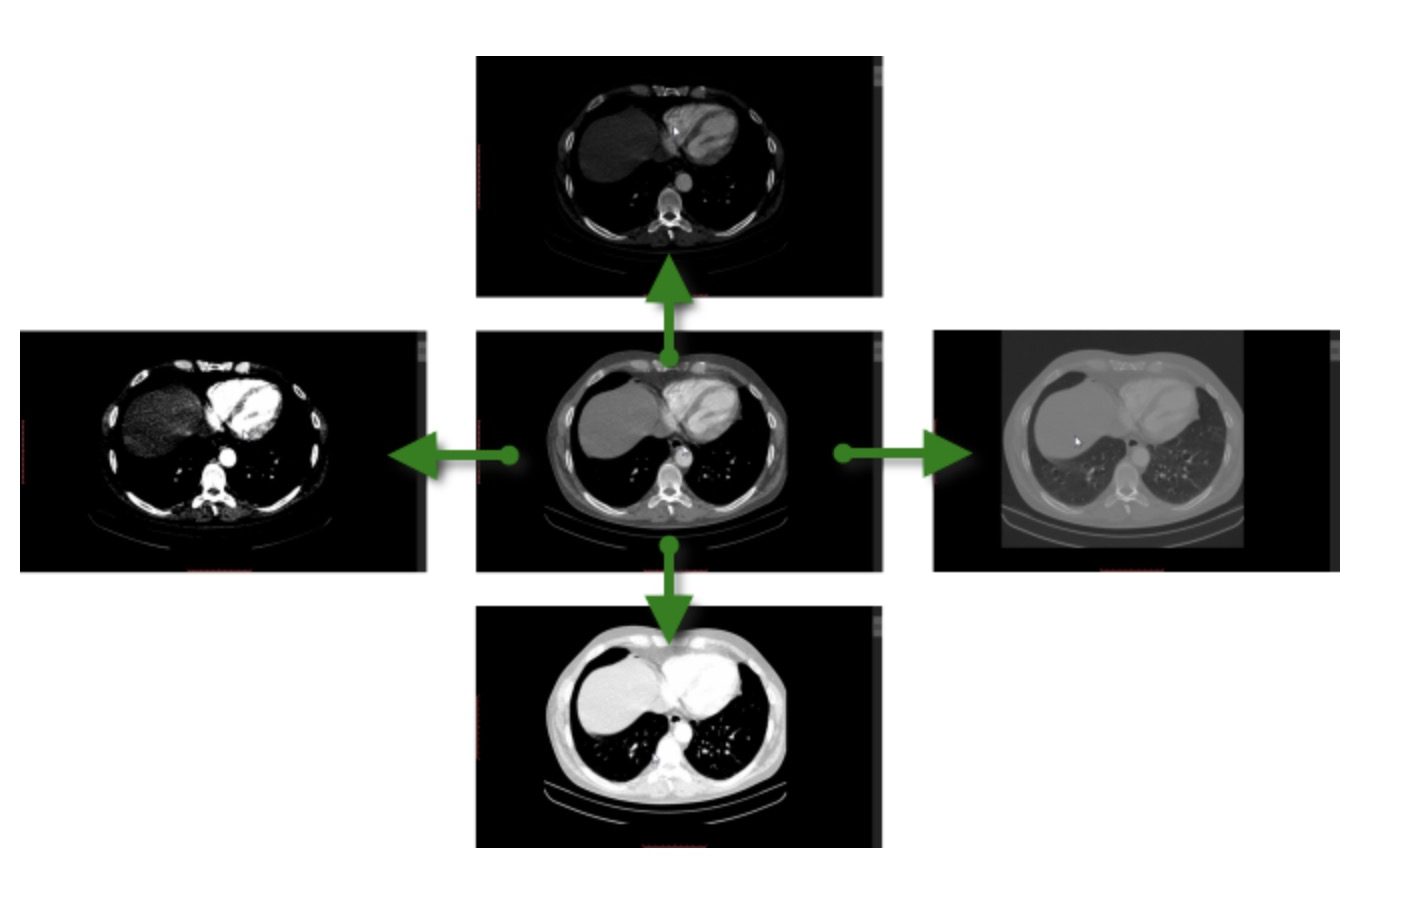

看肺部纵隔窗

胸部ct 肺窗

ct纵隔窗

常规ct肺窗

胸部ct断层解剖(纵隔窗)主动脉根部层面:升主动脉根部已位于纵隔中央

胸部ct解剖